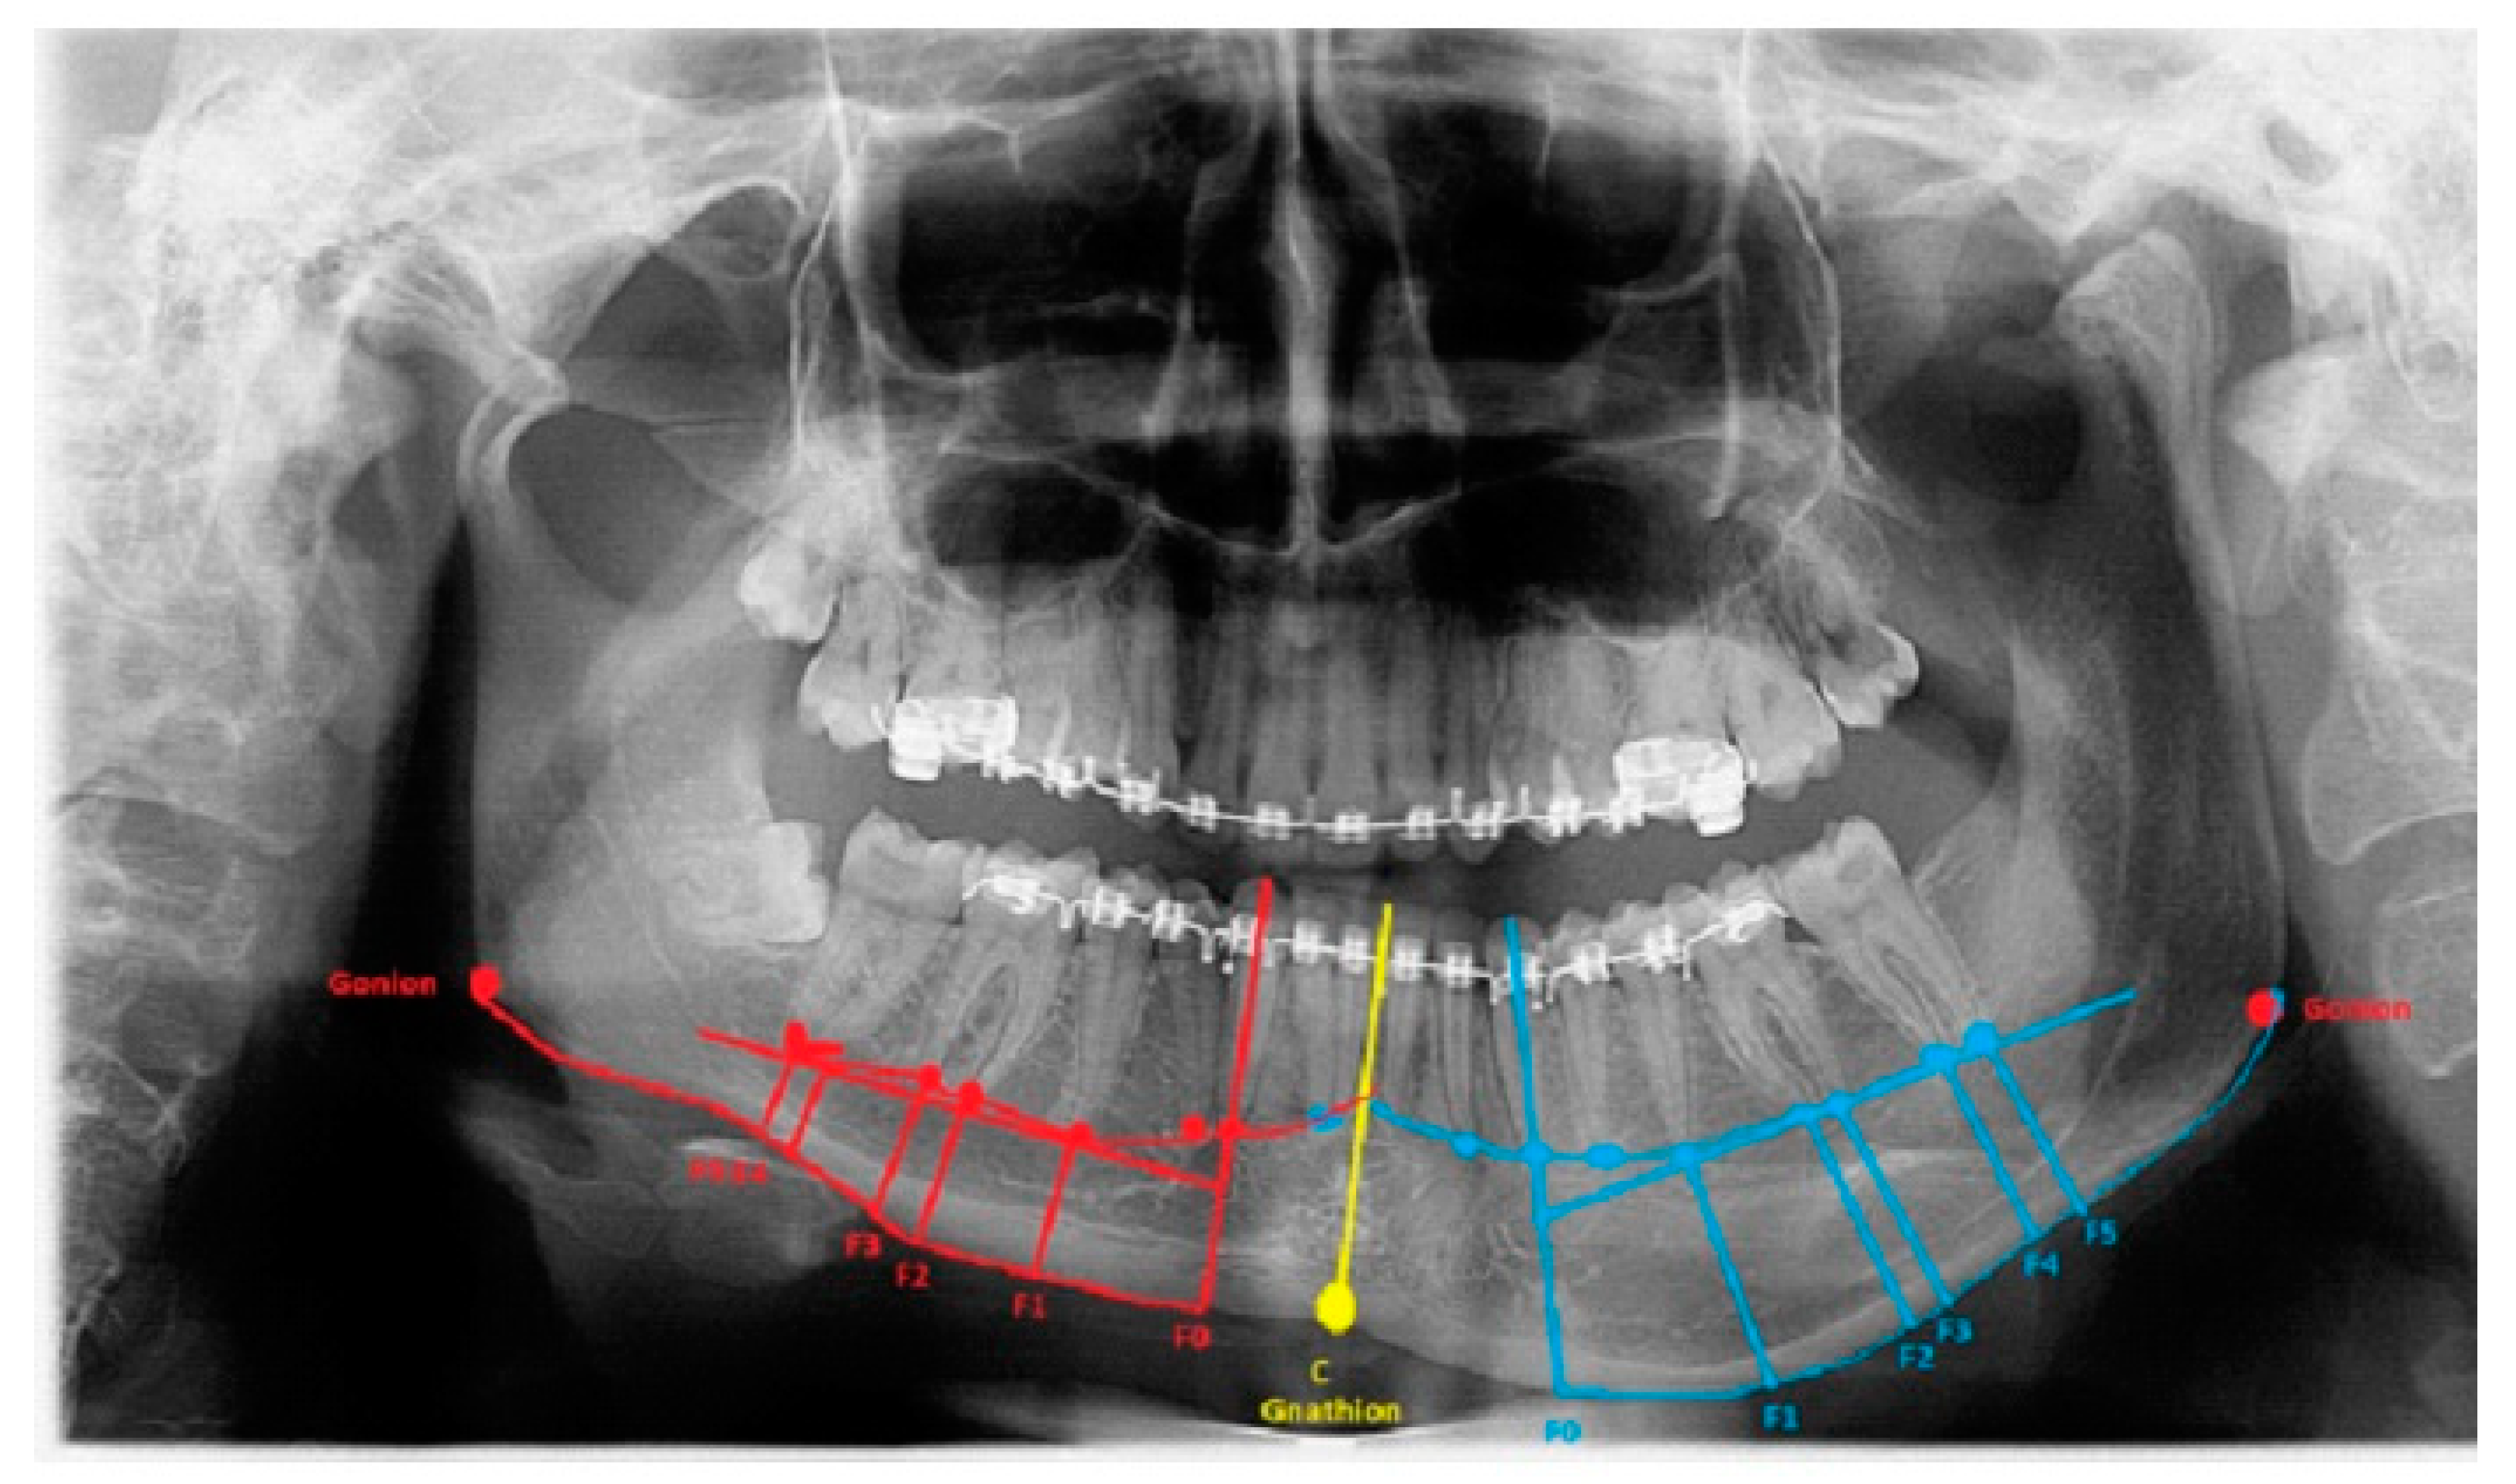

The degree of asymmetry and bone overgrowth varies in each case individually (Figure 2). A classic panoramic radiograph is sufficient to plan the scope of surgery, but because of the natural object enlargement in size by about 15–25%, any detailed measurements are troublesome. Despite this magnification, panoramic visualization enables good estimation of the degree of oversized mandibular bone, which can later be accurately measured on CT/LDCT radiographs. The authors present their proposal for approaches, the usage of which depends significantly on the anatomical-radiological distances (ARD) and proportions. All are based on the six most commonly found situations in CT/CBCT-RTG. Based on the following anatomical-topographical measurements, a protocol for surgical intervention was prepared. Perhaps the presented method of bone measurements will be a valuable study for future surgeries as condylar hyperplasia-related treatment remains without any particular guidelines and remains exceedingly individual. The detailed proposition of approaches based on the author’s proposal and own used anatomical indexes are presented in Table 2. After a detailed radiological data analysis on the RTG/panoramic and lateral cephalogram or LDCT/CT, the following anatomical-radiological proportions should be included for surgical planning:

Figure 2.

Severe form of condylar hyperplasia.

The length between Go-Gn/Go-Gn and the vertical bone volume relation decreases the bone height on the opposite healthy side—the critical point of this technique is the distance between the Go-Go/Go-Gn position and the value of the F0-C bone index. In this case, approach 1C can be used with or without corrective angulotomy/anguloplasty, which reduces the angled volume on the affected side in vertical and horizontal dimensions. If both Go (Right) and Go (Left) are situated on the same horizontal line, no major surgery should be planned, unless performing a condylectomy might relocate the Go point on the affected side to a higher position afterward. Therefore, careful planning in the horizontal plane and the F5: Go measurement can help estimate whether any additional mandibular angle surgery should be planned (Figure 1 and Figure 2; Table 1). This was used in some of the authors’ cases where there was no maxillary bite-plane deviation, and no chin bone asymmetry was present.

The authors conclude that a very severe mandibular overgrowth with increased chin involvement should be a mandatory indication for the classic Ferguson approach with a surgical reduction in the mandibular angle on the affected side [7,13]. The main reason for this is the increased distance and height of the F0:F1 and F0:C:F0 values in this study (Figure 1). The authors fully agree with Ferguson’s approach, which is confirmed in the author’s measurements based on the suggested ARP: IM values and the distances between reference points in the presented study radiographs. Two different cases of one-sided mandibular overgrowths in hemimandibular hyperplasia are drawn and explained in Figure 2.